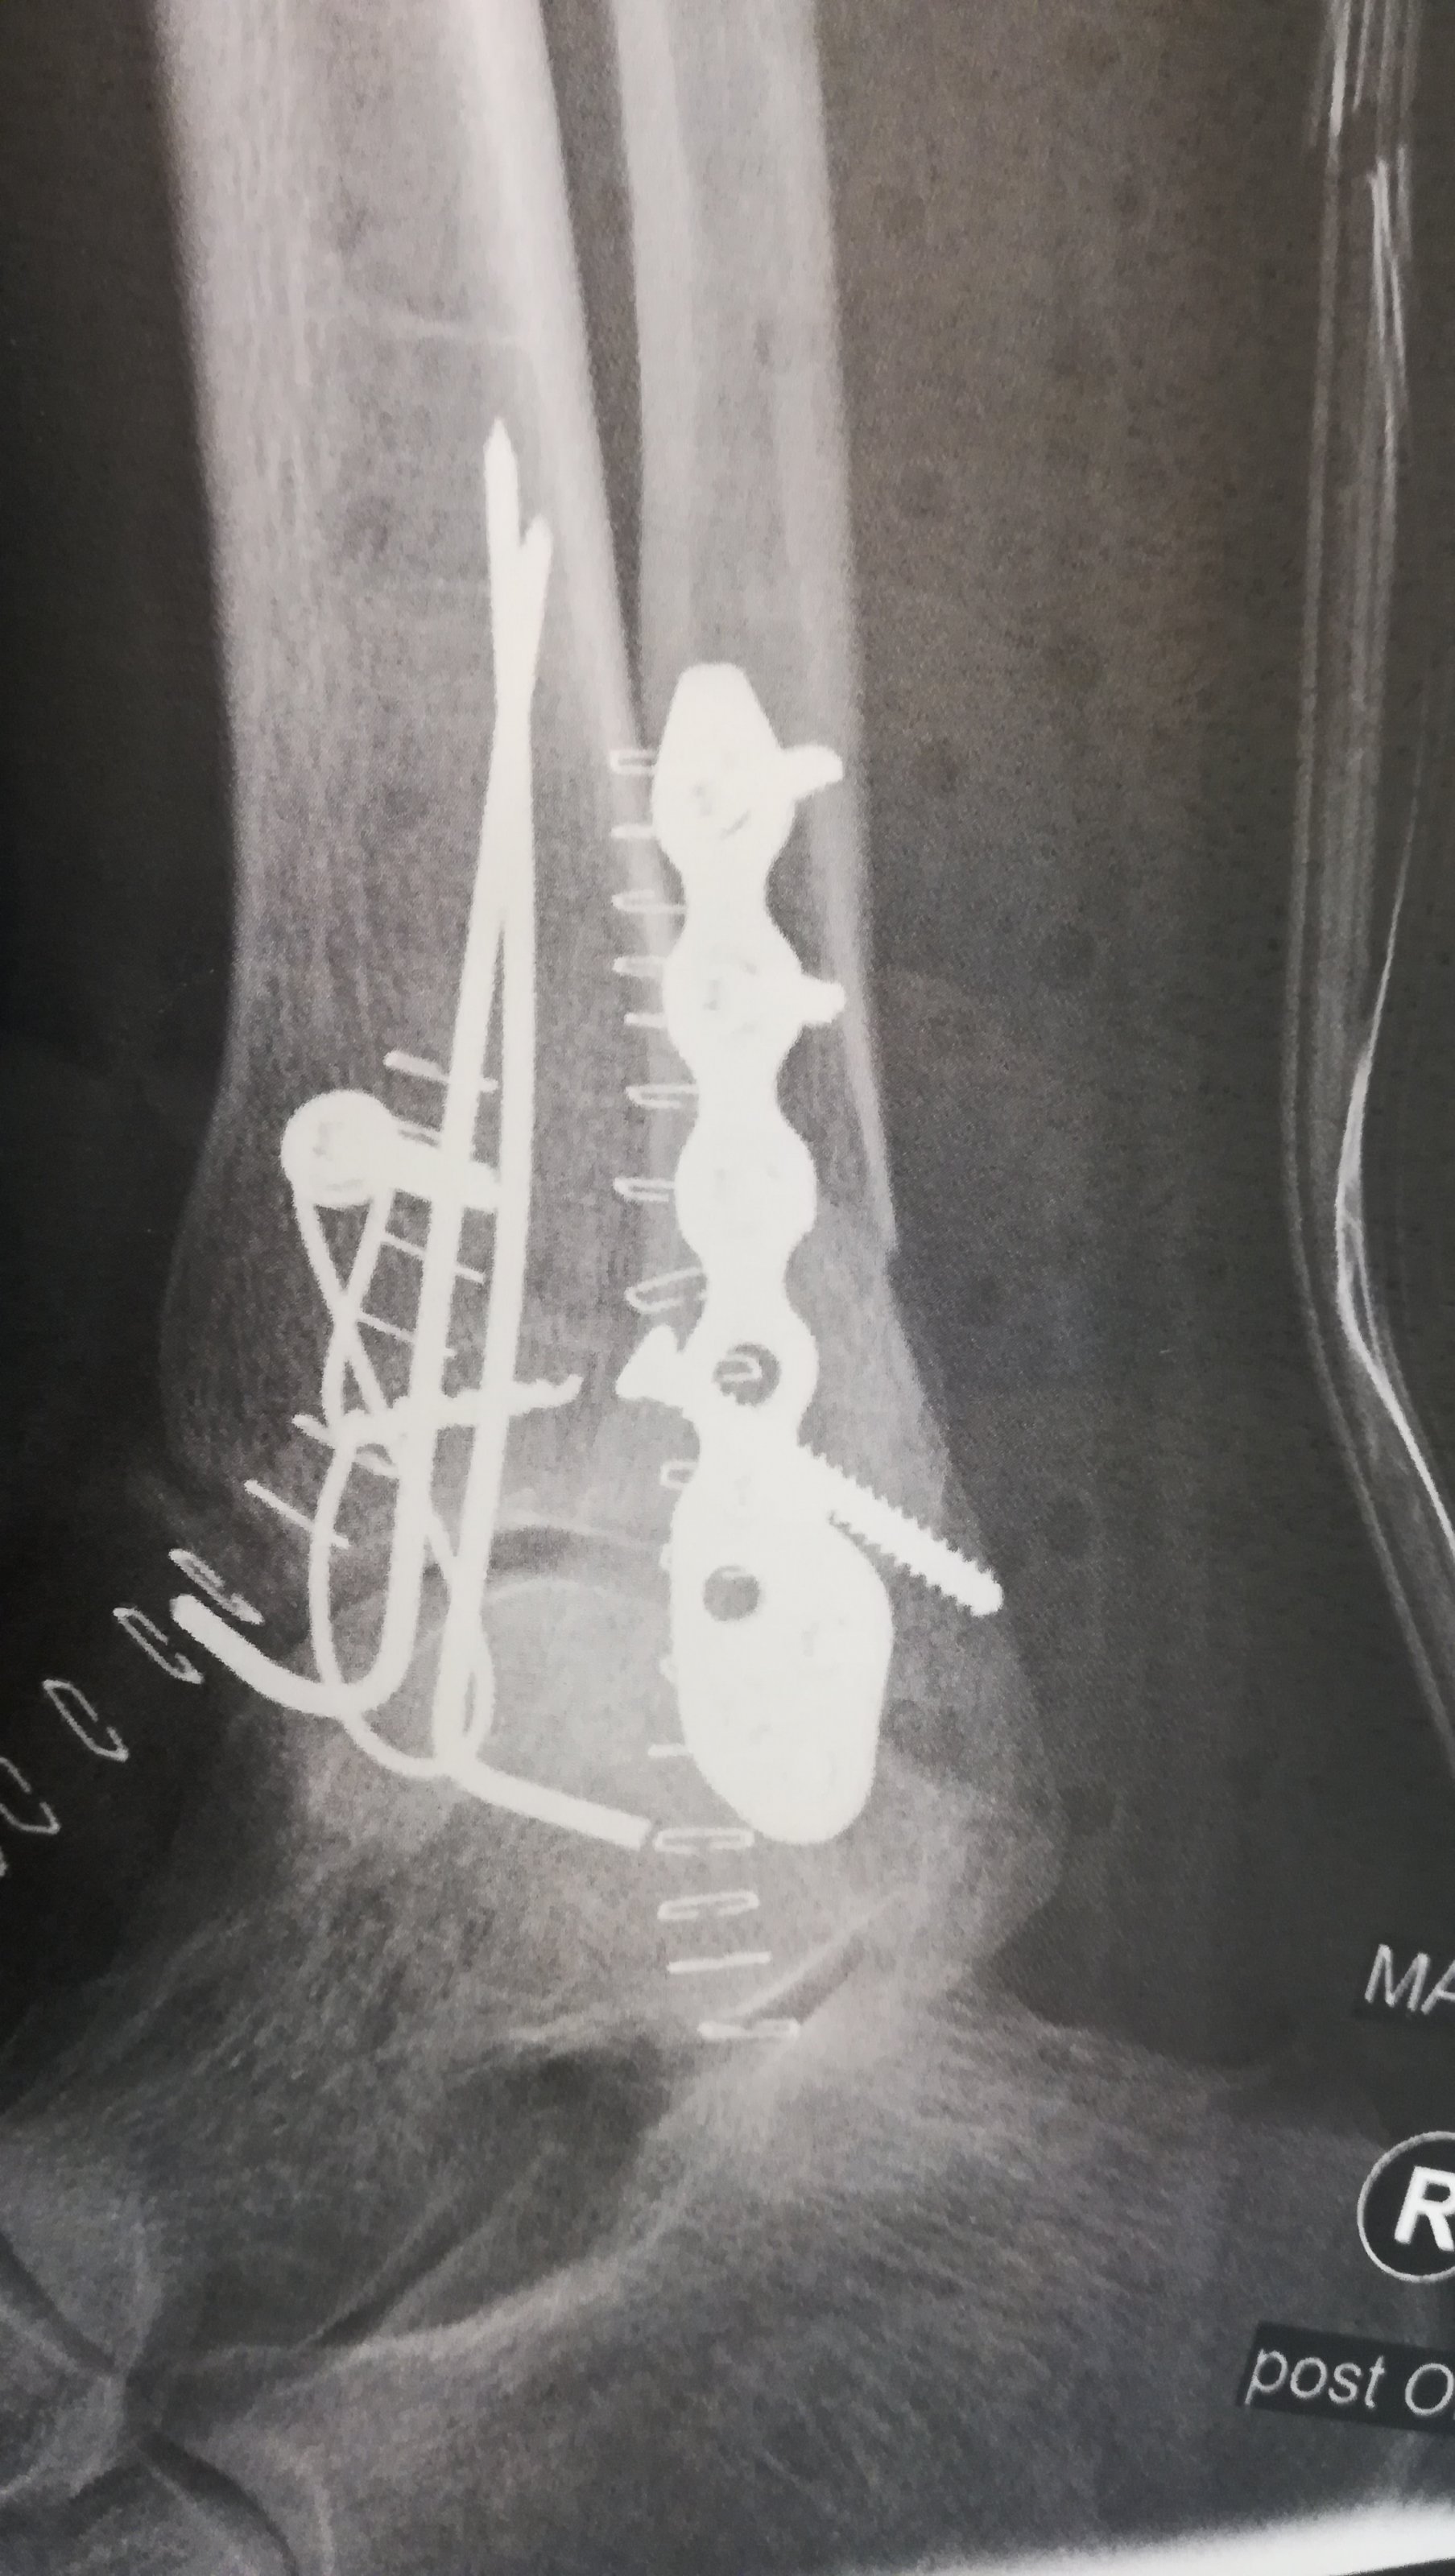

Ein Freund hat sich zum Endurowandern mit seiner knapp ĂŒber 200kg schweren KTM 790 extra stabile Endurostiefel von TT gekauft. Und du wirst es nicht glauben, er hat sich bei einer der ersten Ausfahrten mit der tollen Schutzkleidung Schien- und Wadenbein gebrochen.